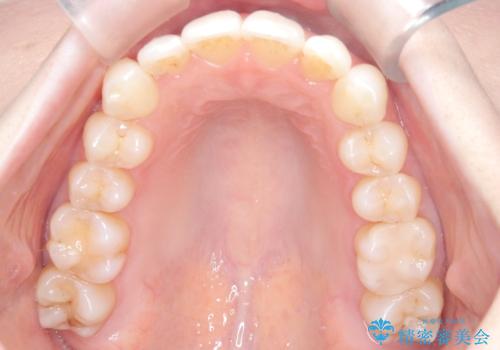

矯正後の後戻りで前歯にガタツキができてしまった インビザラインで改善

- 子どものときにワイヤー矯正をしていたが、後戻りによって前歯のガタツキが気になってきたとのことで来院されました。

アライナー矯正希望だったため、インビザラインによる治療を行いました。

前歯のガタツキを改善する治療法として、マウスピース矯正が適していることが多いです。

マウスピース矯正は、金属製のブラケットやワイヤーを使用せずに、透明なマウスピースを装着して歯を移動させる方法です。そのため、目立たず、痛みも少ないです。